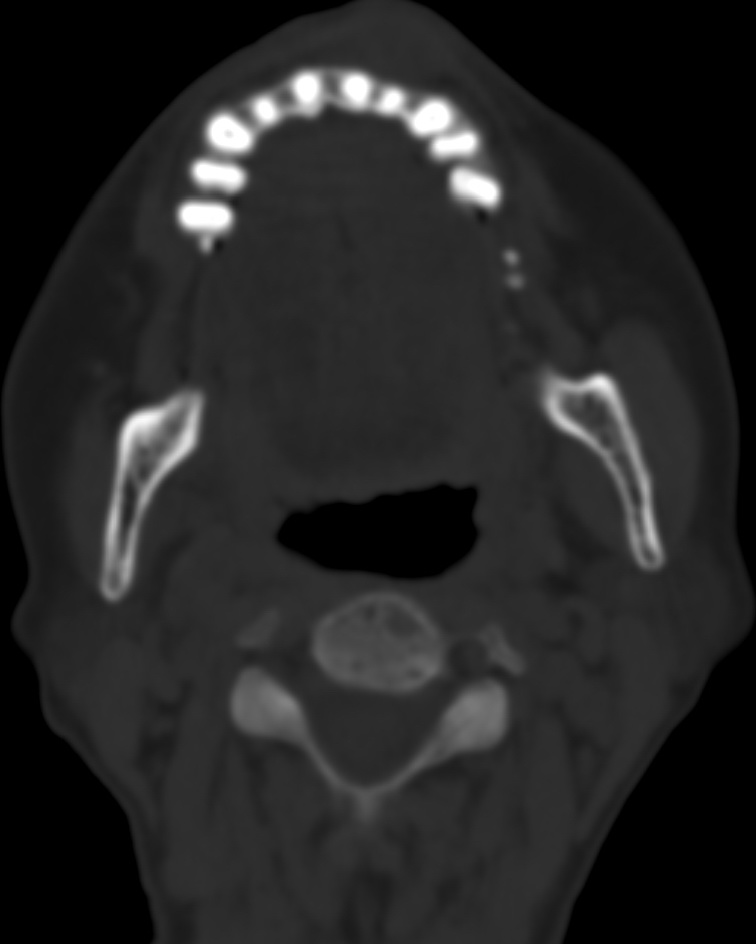

女,68岁。发现上唇无痛性肿块2年多,查体局部皮肤隆起,其余未见异常。

病灶ct值约42hu。

病理结果:唾液腺混合瘤。